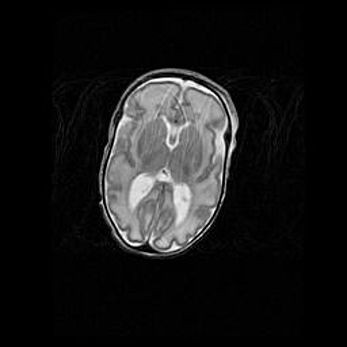

Мальформация Денди-Уокера. Киста задней черепной ямки.

Агенезия мозолистого тела.

Возраст: 2,5 месяца

Вес: 2420 г

Пол: женский

Окружность головы: 37 см

Срок гестации: 32 недели

Мальформация Денди—Уокера — редкий вид патологии ЦНС, представляющий собой врожденный порок развития каудального отдела ствола и червя мозжечка, ведущий к неполному раскрытию срединной (Мажанди) и латеральных (Лушка) апертур IV желудочка мозга. Для этогно синдрома характерна триада симптомов: гипотрофия червя мозжечка и/или полушарий мозжечка, кисты задней черепной ямки, гидроцефалия различной степени. В 70% случаев порок сочетается и с другими аномалиями головного мозга, в частности с агенезией мозолистого тела.